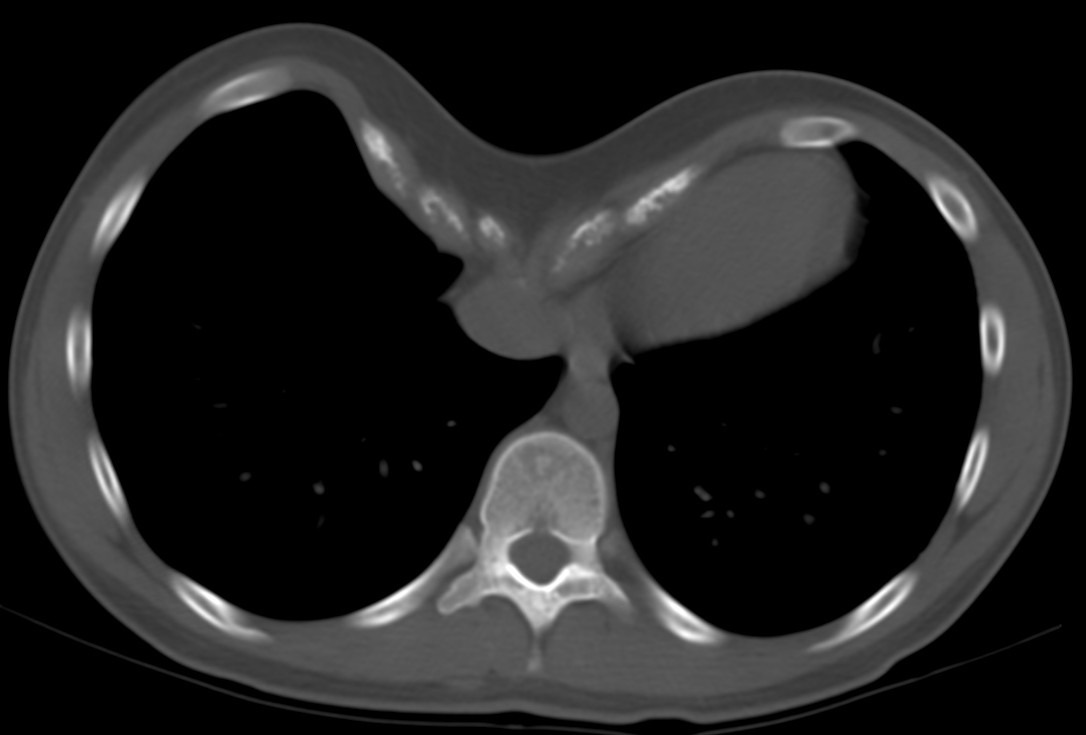

CASO: cáncer de mama. Control anual.

Hallazgos:

- Se observa un aumento de densidad con agrupación broncovascular que produce un borramiento del borde cardicaco derecho; hallazogos compatibles con atelectasia en el lóbulo medio. Véase el TC a continuación: